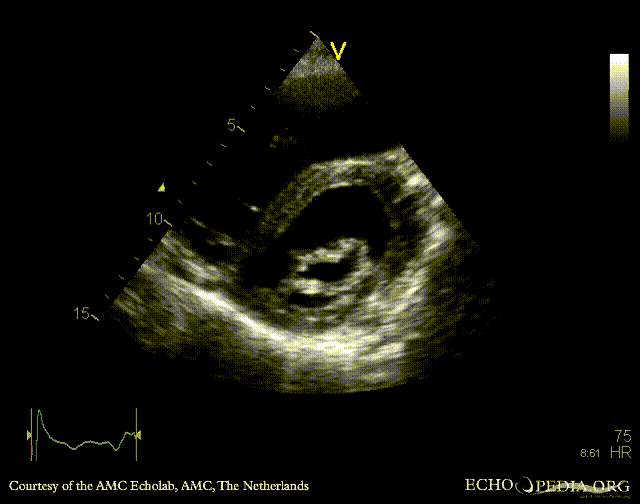

A4CH: enlarged atria and ventricles A3CH: severe aortic and mitral regurgitation